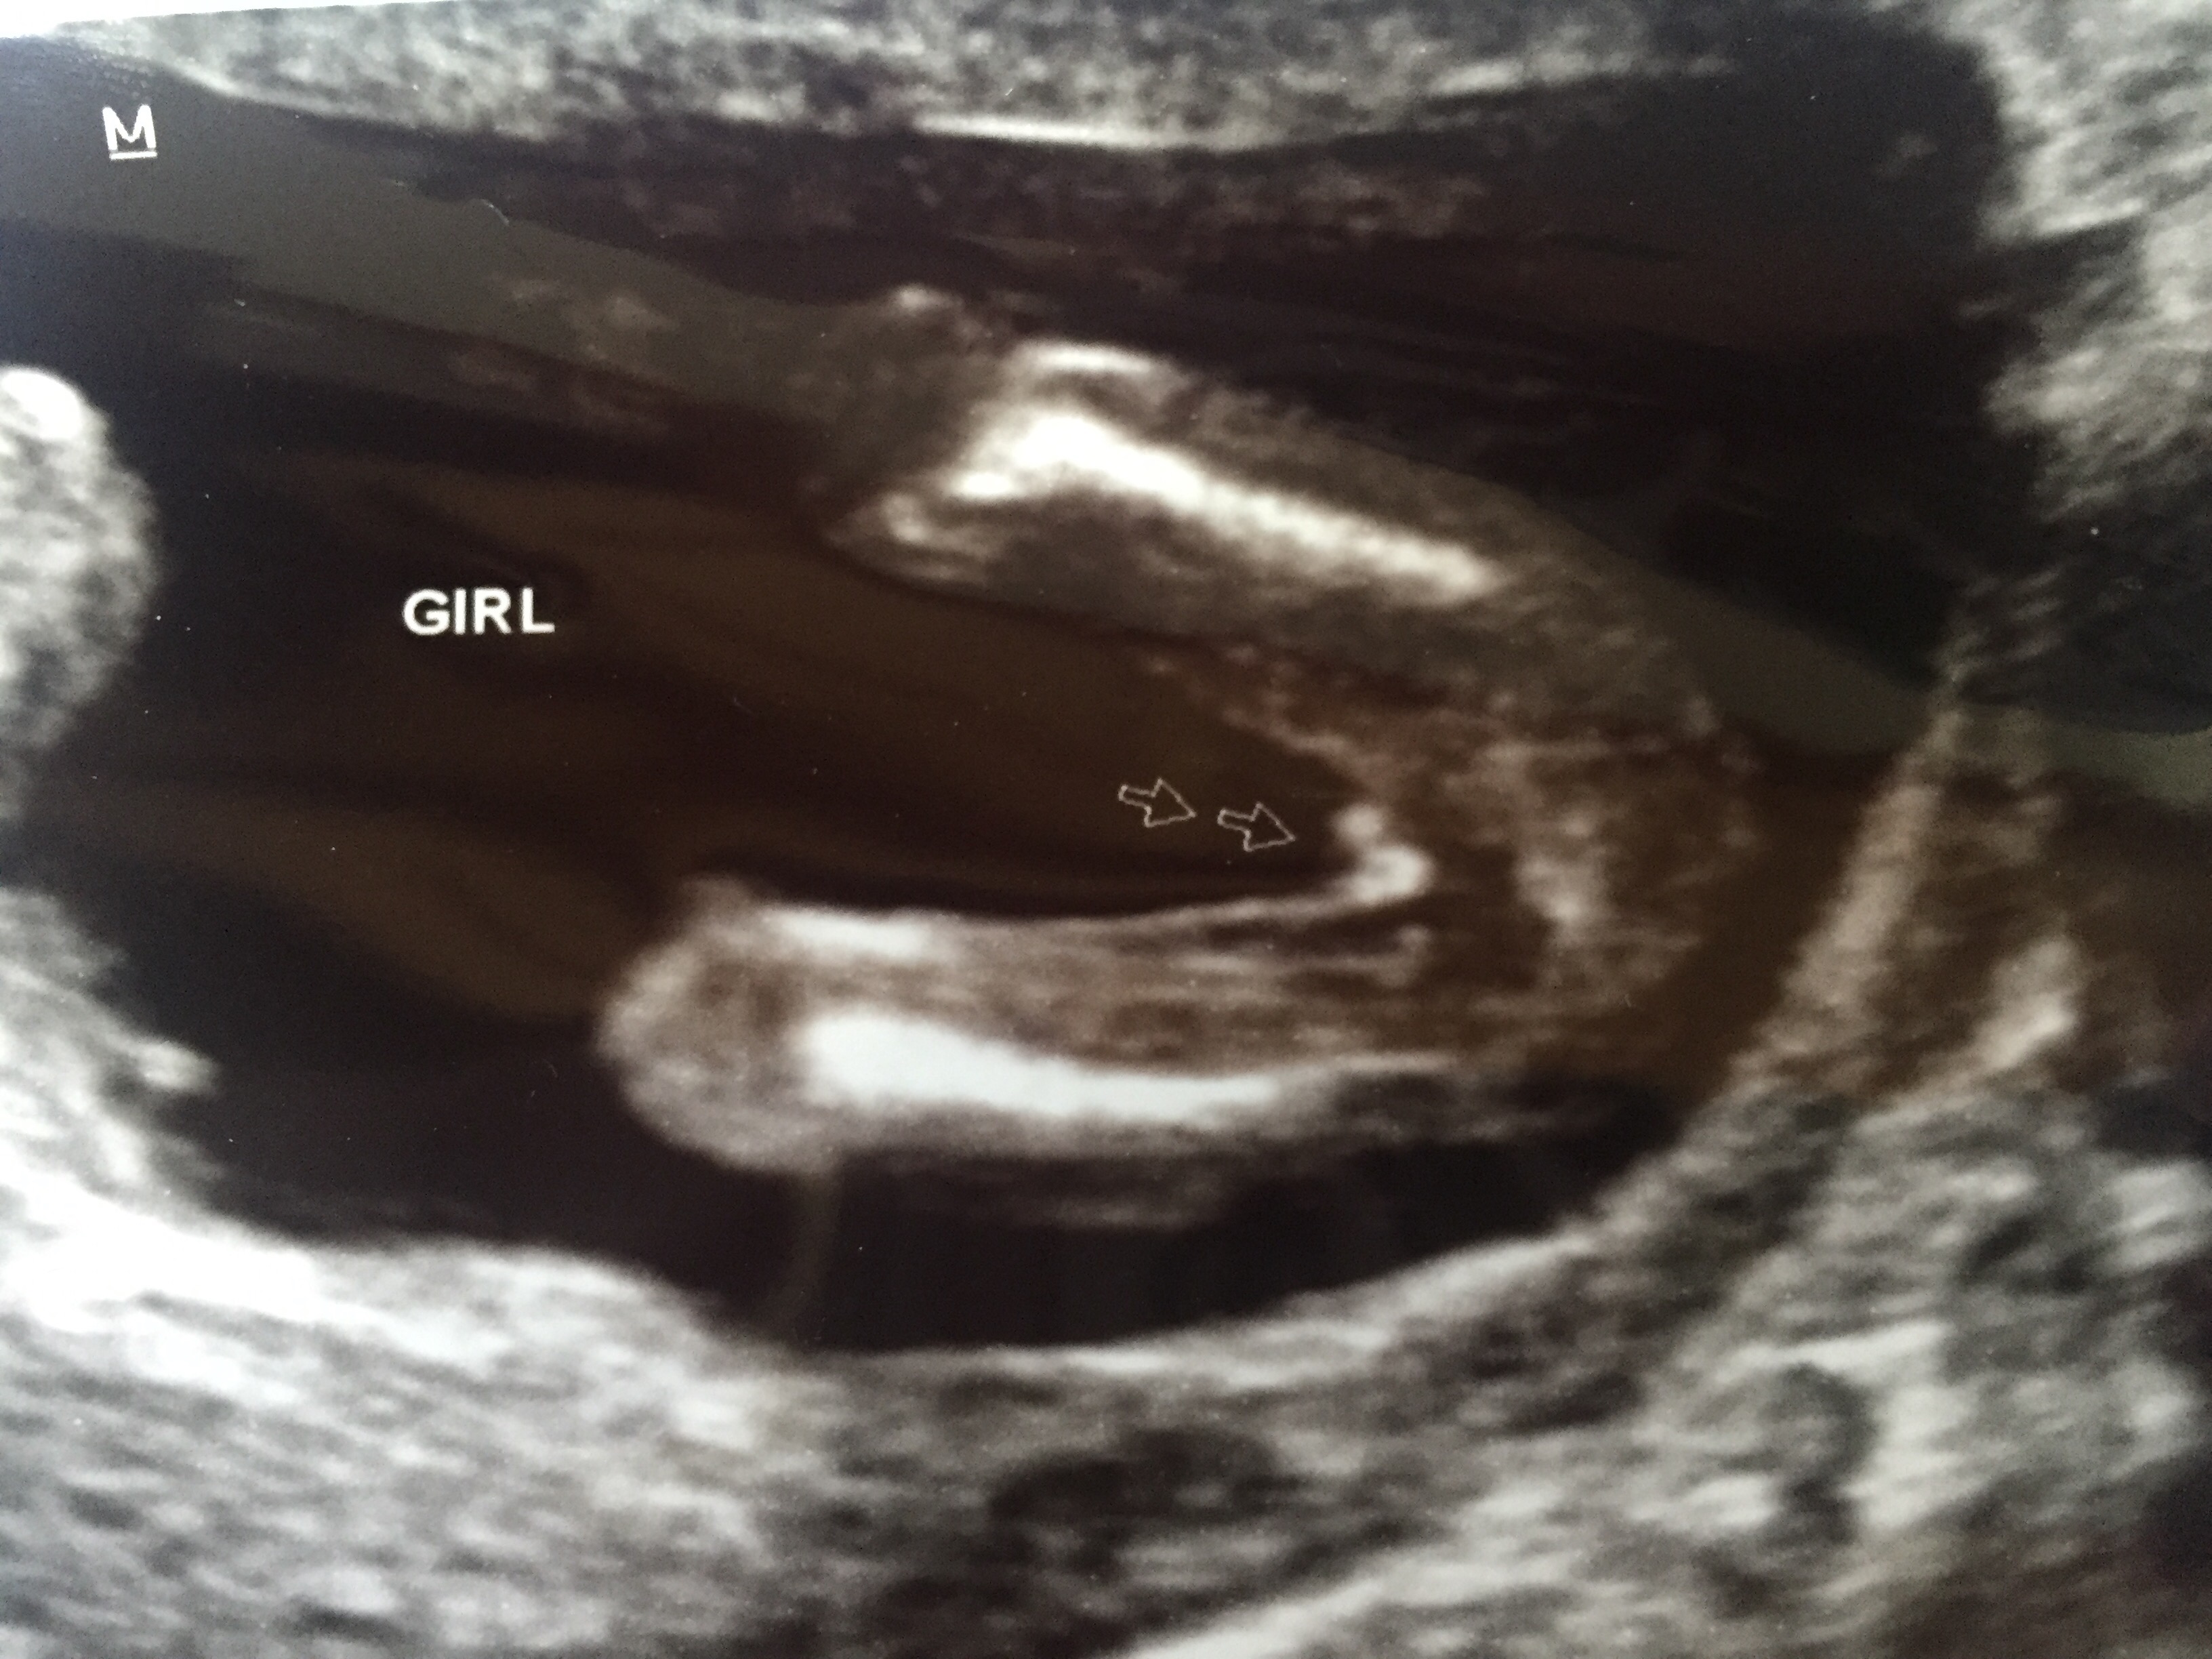

Hi Everyone! I had an ultrasound today at 15 weeks, 2 days. The tech told me I'm having a girl. Do y'all agree? I guess I need extra reassurance after two boys! :)

Looks pretty girly to me. Boys are normally quite obvious with something sticking out there!